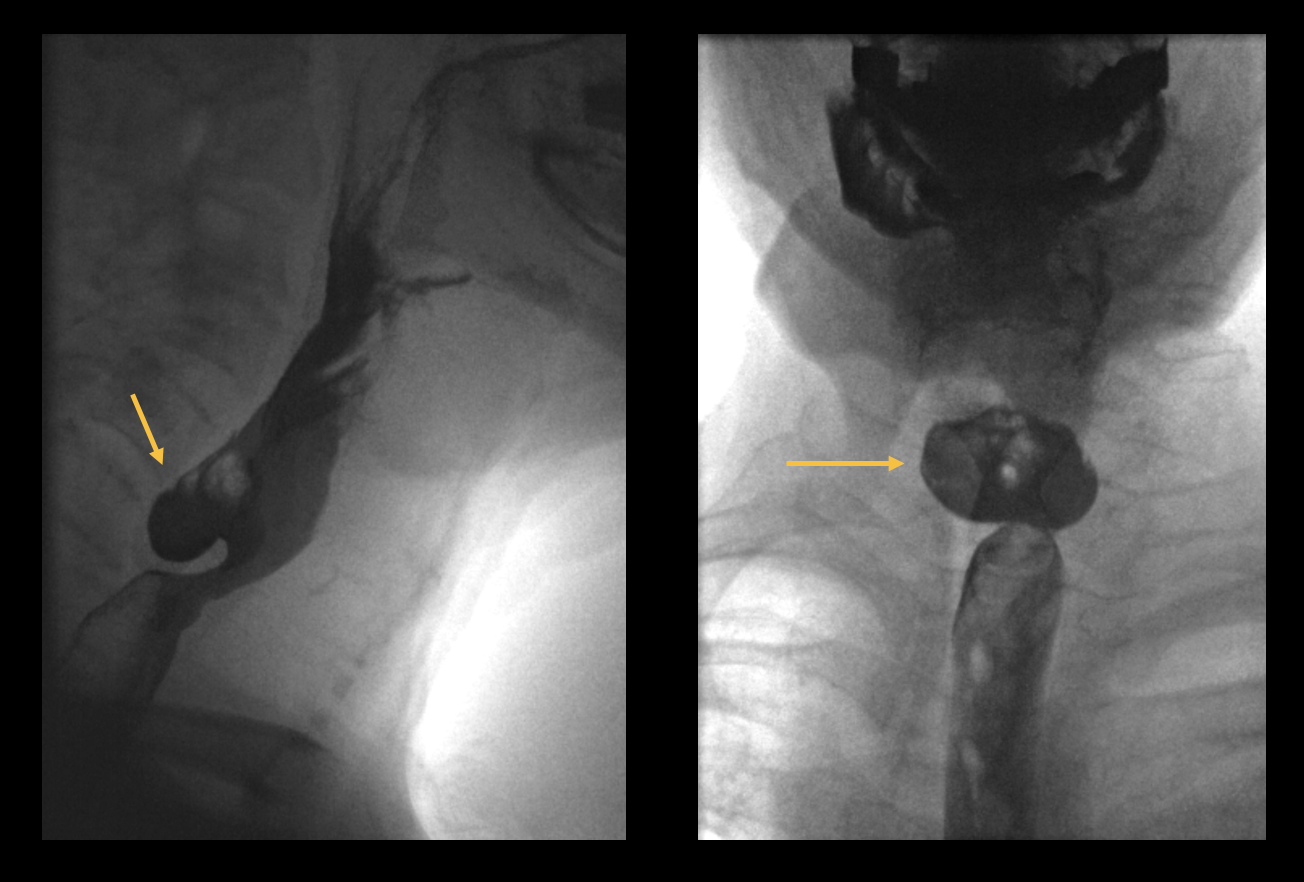

Auf den folgenden Abbildungen handelt es sich um einen Patienten, der in die Klinik eingewiesen wurde, mit stärksten Kopfschmerzen und Übelkeit. In der MRT sowie in der Angiographie zeigt sich eine arteriovenöse Malformation (AVM).

Eine AVM ist eine angeborene Gefäßmissbildung mit Shunt-Verbindungen (Nidus) zwischen zerebralen Arterien und Venen ohne zwischengeschaltetes Kapillarbett. Arteriovenöse Malformationen können zeitlebens asymptomatisch bleiben. Häufig manifestieren sie sich jedoch zwischen dem 20. und 40. Lebensjahr mit Kopfschmerzen. Intrakranielle Blutungen treten bei ca. 50 bis 60 % der Patienten, epileptische Anfälle und fokal-neurologische Defizite bei ca 25 % der Betroffenen auf. Die klassische Therapie ist die operative Resektion, wobei auch zunehmend endovaskulär behandelt wird.

Bild 4: Axiale und koronale MRT-Bilder, sowie digitale Subtraktionsangiographie mit Darstellung der Shunt-Verbindungen zwischen den Arterien und Venen. Der Nidus ist durch die Pfeiler markiert.